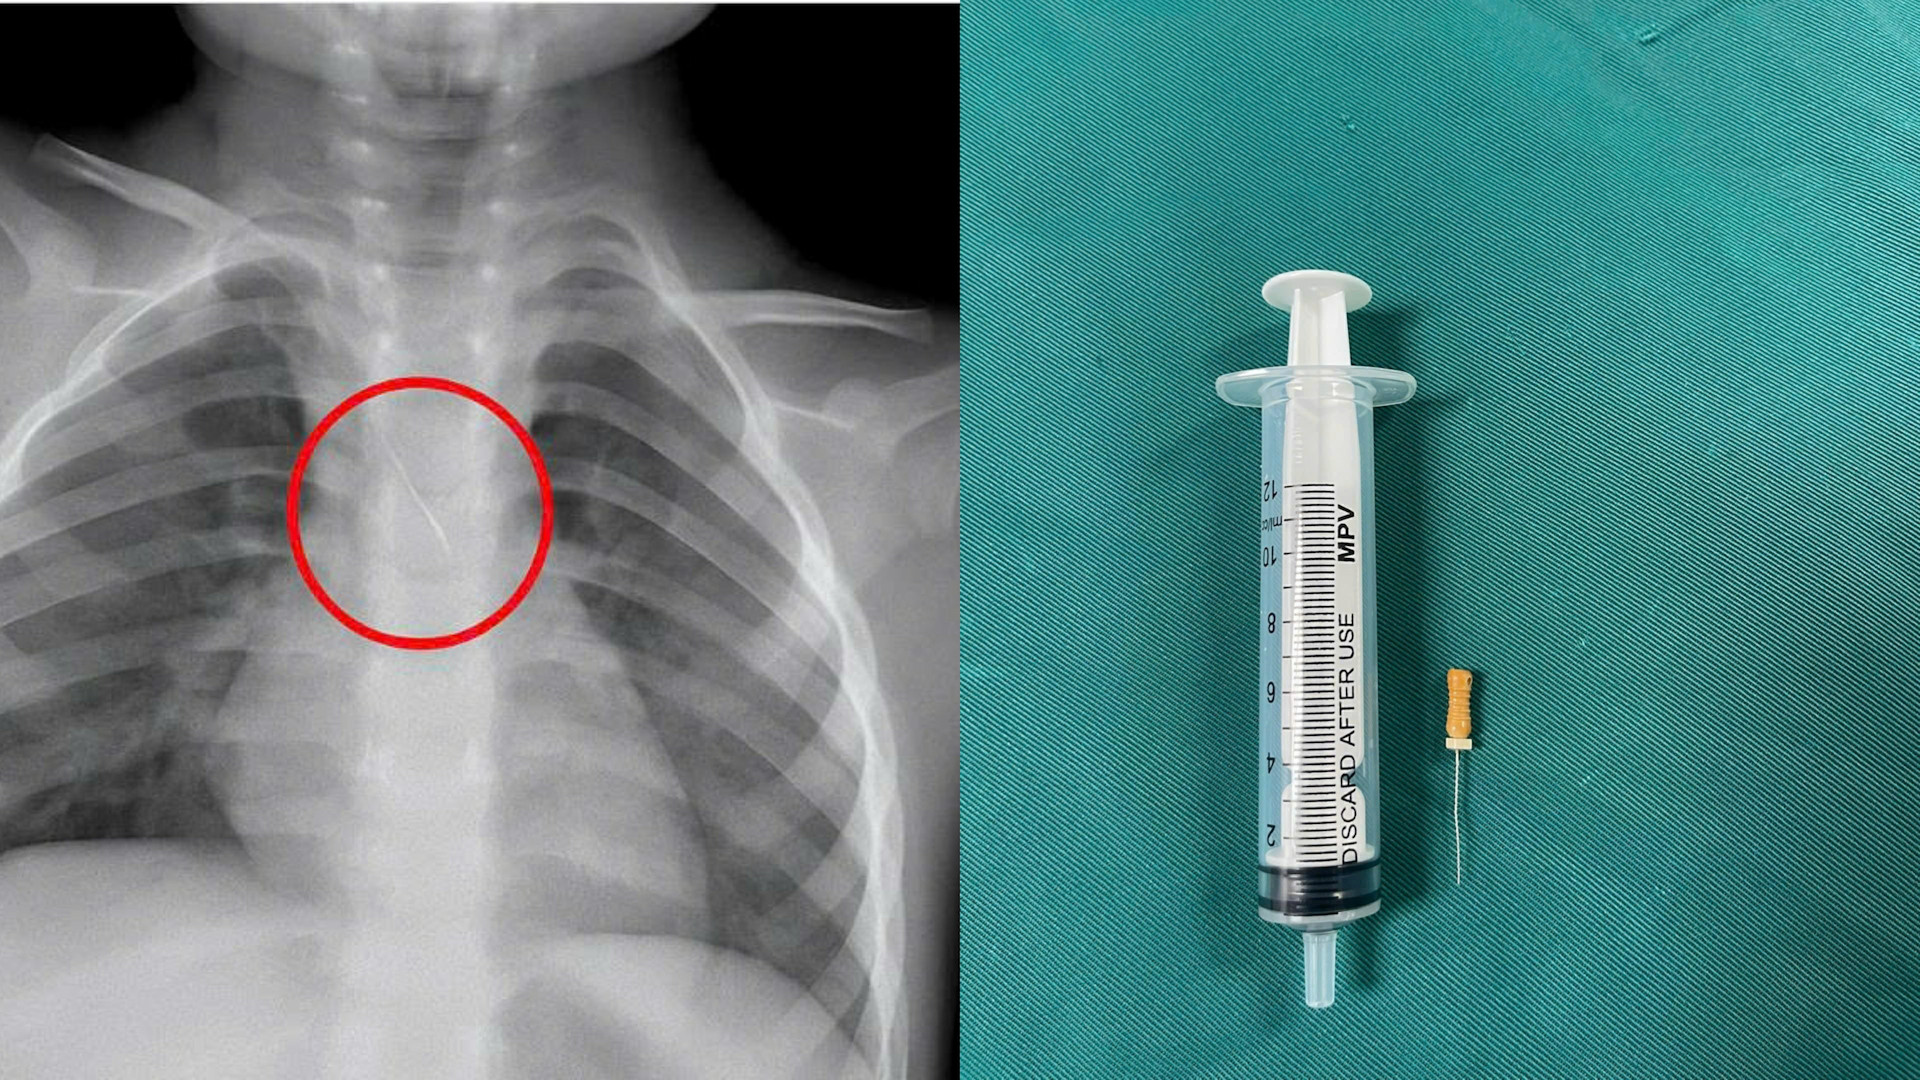

Trước đó, bệnh nhi N.Q.T.Đ. (3 tuổi, trú tại xã Cửa Việt) nhập viện trong tình trạng ho nhiều, ho sặc. Kết quả chẩn đoán hình ảnh cho thấy, bệnh nhi bị sặc kim chọc tủy vào đường thở.

Dị vật này dài khoảng 22mm, nằm ở góc carina (nơi vùng chia đôi khí quản), một đầu nhọn cắm vào 1/3 dưới khí quản, một đầu tròn nằm trong phế quản gốc trái.

Dị vật trong đường thở của bệnh nhi. Ảnh: BVCC